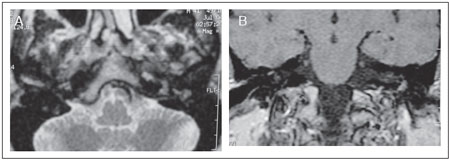

Patient 2 was a 41-year-old man who presented with unilateral conductive hearing loss. CT scan showed a middle ear mass in the promontory mimicking a tympanic paraganglioma (Figure 4). Magnetic ressonance imaging (MRI) of the temporal bones revealed a small mass in the left tympanic cavity with isosignal in T1 and post-contrast enhancement on T2 sequences(Figure 5). The patient underwent surgical intervention through a supra-meatal approach that completely removed the mass. The tumor was brownish and elastic, involved the ossicles and extended to the promontory. Histology and immunohistochemical reactions were also compatible with middle ear adenoma with neuroendocrine differentiation (Figure 6).

Figure 4. Computed tomography of the temporal bones revealing a small soft tissue density material in the left tympanic cavity. A. Coronal B. Axial

Figure 5. A: MRI of the temporal bones revealing a small mass in the left tympanic cavity with isosignal in T1 (A) and post-contrast enhancement on T2.